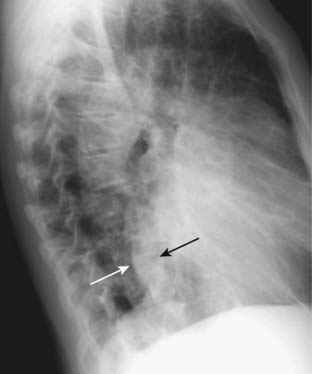

image

Figure 9-3 Enlargement of the cardiac silhouette in the lateral projection.

In most normal patients, the posterior border of the heart does not overlap the thoracic spine. In this patient with cardiomegaly, the posterior border of the heart (solid white arrow) overlaps the anterior border of the thoracic spine (solid black arrow). Estimation of cardiac size is best made on the frontal projection, but the lateral projection can be used for a confirmatory sign of enlargement of the cardiac silhouette.